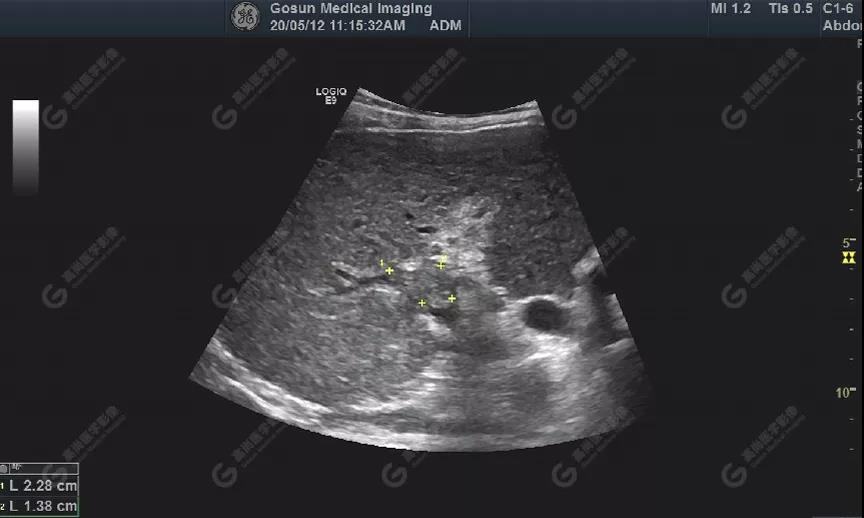

肝包膜不光滑,內(nèi)部回聲增粗、分布不均勻

門靜脈右支管腔內(nèi)見(jiàn)大小約23mm×14mm實(shí)性低回聲充填

超聲所見(jiàn)肝包膜不光滑,實(shí)質(zhì)回聲增粗,不均勻,以右葉顯著,肝內(nèi)可見(jiàn)散在高回聲結(jié)節(jié),最大約7mm×5mm,邊界清,形態(tài)規(guī)則,CDFI顯示高回聲結(jié)節(jié)未見(jiàn)明顯異常血流信號(hào)。門靜脈主干內(nèi)徑約14mm,門靜脈右支管腔內(nèi)見(jiàn)實(shí)性低回聲,大小約23mm×14mm,邊界不清,形態(tài)不規(guī)則,局部與肝組織分界不清,CDFI:門靜脈主干血流緩慢,左支血流充盈好,右支血流充盈缺損,低回聲內(nèi)未見(jiàn)明顯血流信號(hào)。超聲造影:經(jīng)左側(cè)肘靜脈團(tuán)注超聲造影劑sonovue2.0ml。肝組織開始增強(qiáng)時(shí)間8秒,病灶開始增強(qiáng)時(shí)間11秒,邊界清晰。脈期呈均勻高增強(qiáng),至門脈期和延遲期消退為低增強(qiáng)。延遲期肝S7段局部回聲減低,范圍約82mm×50mm,內(nèi)見(jiàn)一低增強(qiáng)區(qū),范圍約13mm×16mm。